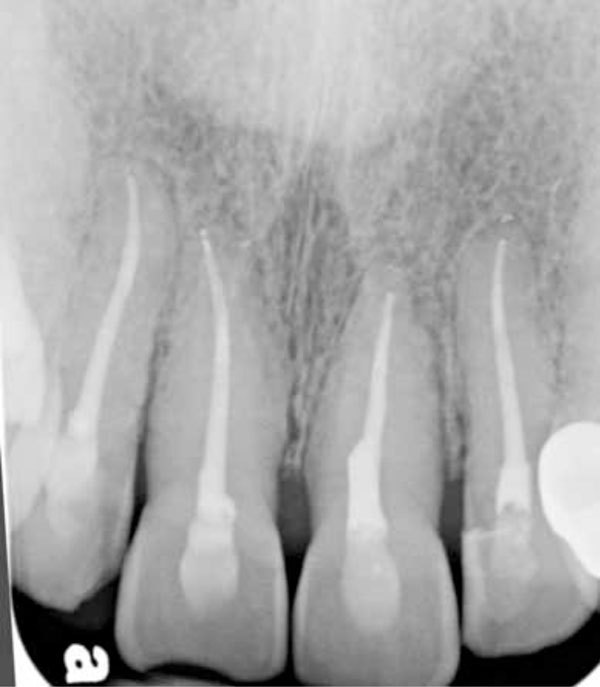

Periapical radiograph showing the teeth after root canals on all four incisors.

Root canal therapy was performed on teeth #12, 11, 21, and 22 to relieve the pain and enable retention of the teeth (Figs. 8 and 9). The root canals were done two at a time, in a total of two visits (7/18/2012 and 8/16/2012). Composite restorations were then placed (10/18/2012) to close the access preparations and repair the fractured areas of her front teeth (Figs. 8 and 9).